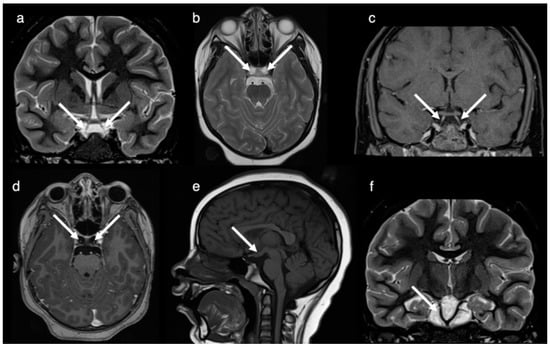

2. Case Report